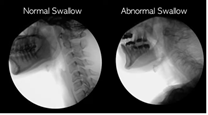

Dysphagia is the difficulty or sensation of having difficulty swallowing certain foods, liquids, medicines or saliva.

Difficulties can occur in any of the three phases of swallowing. It can be classified according to the location of them.